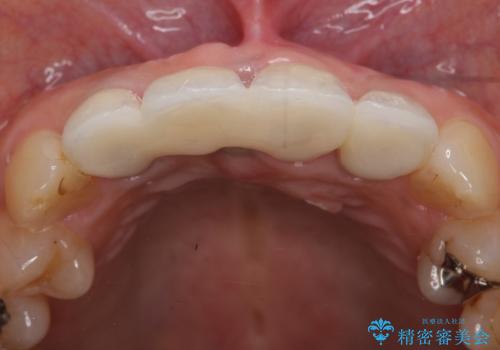

- 右上の前歯が折れてしまったので診て欲しいといらっしゃった方の症例です。

右上1番目の歯は保存不可能だったため抜歯し、ブリッジによる補綴を行いました。

前歯の補綴ではオールセラミッククラウンを希望される患者様が多いですが、オールセラミッククラウンの中でも、エコノミー、スタンダード、スペシャル、エクセレントとランクがあります。

その中でも特に審美性が高いのがスペシャル、エクセレントです。スペシャル、エクセレントは口腔内写真をもとに熟練の技工士が、患者様の口腔内に合わせたオーダーメイドのクラウンを製作致します。